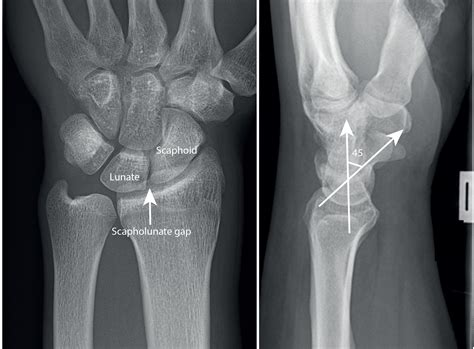

Here is a table outlining common findings in a Normal Wrist Xray:

Finding Description

Normal Bone Density Bones appear uniform and dense without any signs of thinning or erosion.

Fracture Visible break or crack in the bone, often accompanied by misalignment.

Dislocation Bones are out of their normal position, often due to trauma.

Arthritis Joint space narrowing, bone spurs, and other signs of wear and tear.

Soft Tissue Swelling Increased density around the joints, indicating inflammation or injury.

• Fractures: Common in the scaphoid, radius, and ulna bones.

• Dislocations: Often involving the lunate or other carpal bones.